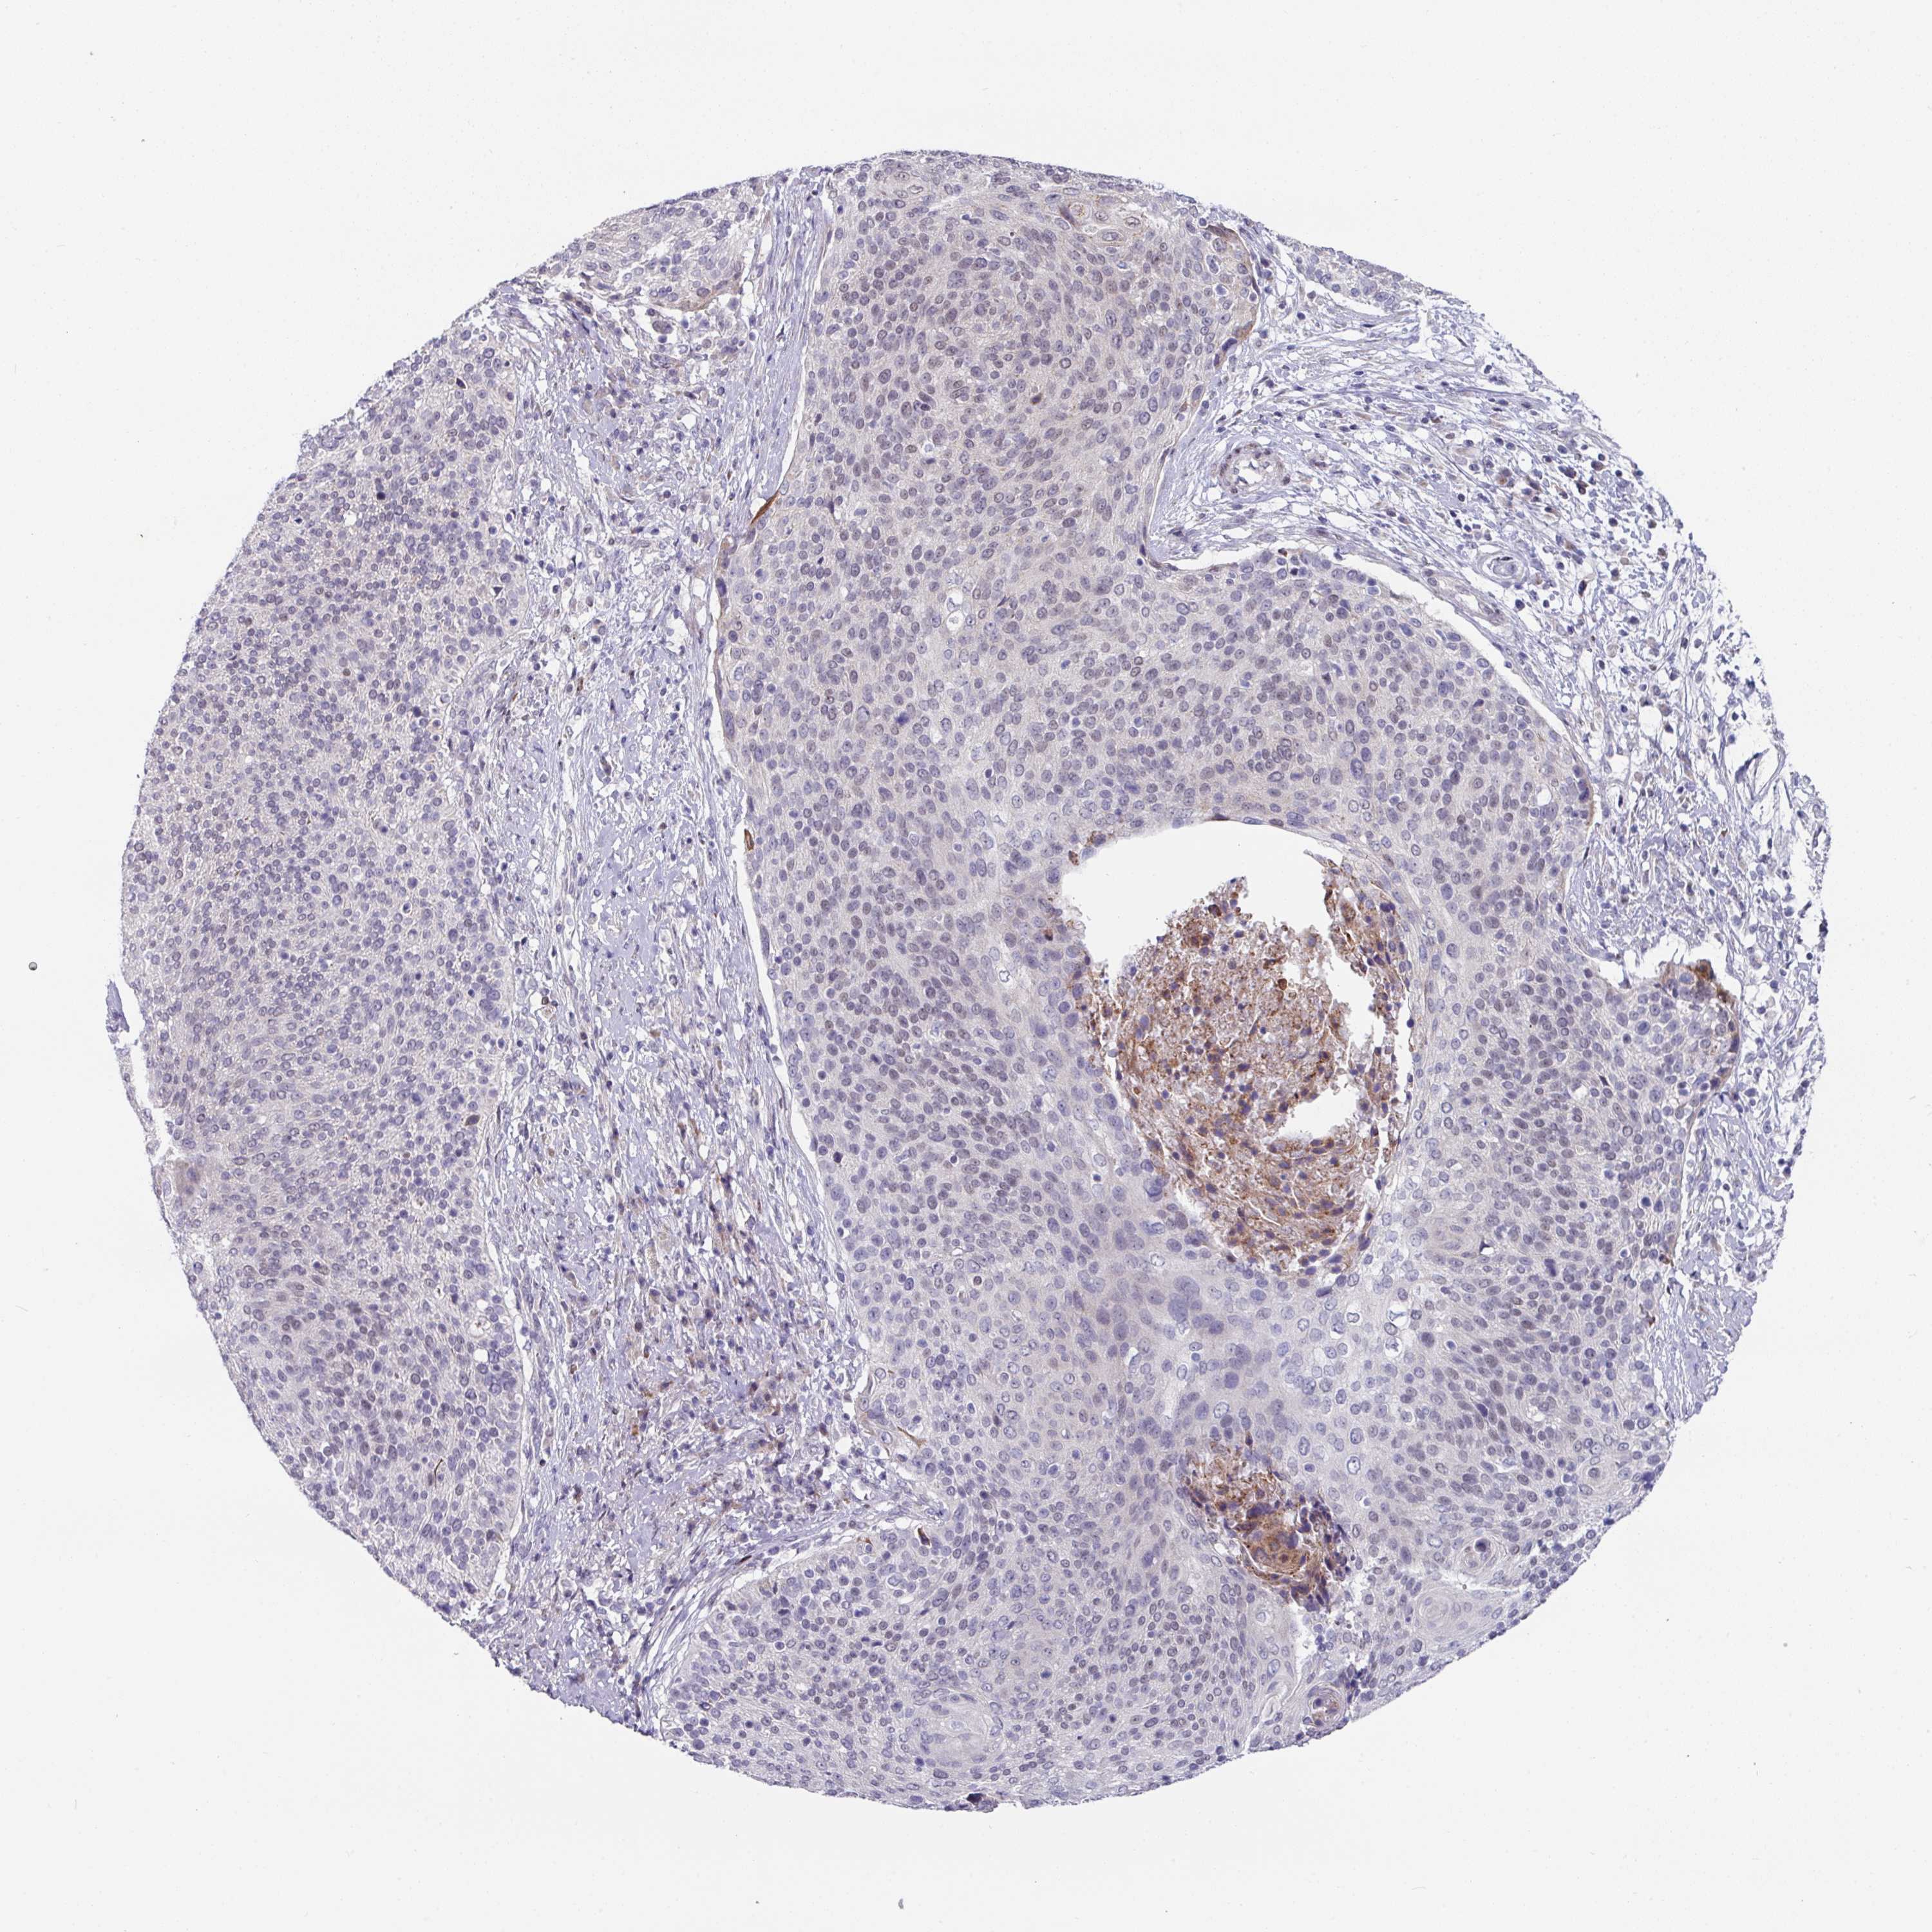

CERVICAL CANCER - Protein expressioni

A mouse-over function shows sample information and annotation data. Click on an image to view it in a full screen mode. Samples can be filtered based on level of antibody staining by selecting one or several of the following categories: high, medium, low and not detected. The assay and annotation is described here.

Note that samples used for immunohistochemistry by the Human Protein Atlas do not correspond to samples in the TCGA dataset.

Antibody stainingi

Antibody staining in the annotated cell types in the current human tissue is reported as not detected, low, medium, or high, based on conventional immunohistochemistry profiling in selected tissues. This score is based on the combination of the staining intensity and fraction of stained cells.

Each image is clickable and will lead to virtual microscopy that enables deeper exploration of all samples and also displays staining intensity scores, fraction scores and subcellular localization as well as patient and tissue information for each sample.

Antibody HPA048677

Antibody HPA056480

Antibody CAB011574

Staining

High

Medium

Low

Not detected

Intensity

Strong

Moderate

Weak

Negative

Quantity

>75%

75%-25%

<25%

None

Location

Nuclear

Cytoplasmic/membranous

Cytoplasmic/membranous,nuclear

Adenocarcinoma, NOS